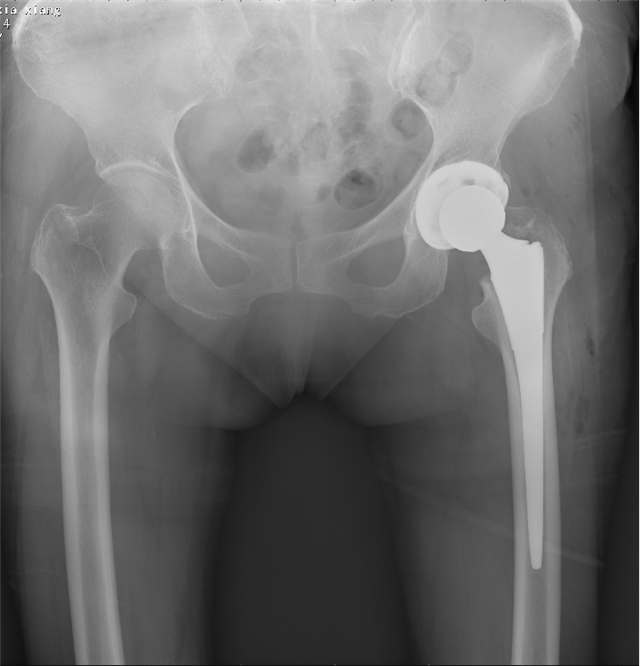

治疗后

陈女士1年前因左股骨颈骨折在创伤骨科与手外科住院,并由陈跃平主任主刀完成左人工全髋关节置换术,术后恢复效果佳,不久后便痊愈出院,关节功能恢复良好。后来,陈女士姐姐同样因为外伤导致了左股骨颈骨折,受伤后在当地医院住院治疗,当陈女士得知姐姐病情后,毫不犹豫地推荐她转到广西中医药大学附属瑞康医院创伤骨科与手外科进行治疗,并一再强调让龙飞攀医生主管。她经常把陈主任和龙医生挂在嘴边:"陈主任和龙医生真是很好,不但手术做得好,人也很随和,完全不把我们当病人看待,就像亲人一样。"

姐姐从靖西转上来后,经过一系列术前检查评估与准备,陈跃平主任带领团队为其顺利完成左人工全髋关节置换术,术后在医护人员的精心指导及护理下顺利出院。出院后,龙医生及责任护士不时电话回访,关心她康复的进度。如今,姐姐髋关节功能恢复良好,她就迫不及待嘱咐陈女士给医护人员送来锦旗,还说两姐妹又能相约跳广场舞了。看着病人和家属眼含热泪的笑脸,创伤骨科与手外科全体医护人员由衷地感到高兴,因为有了她们的信任与支持,让所有的医护人员更有了前进的动力。都说"金碑、银碑,不如老百姓的口碑。"正是因为有了精湛的技术,良好的医德,创伤骨科与手外科团队把患者当成自己的亲人,把患者的需求作为工作的中心,把患者的健康作为最大的目标,才有了口口相传的口碑。